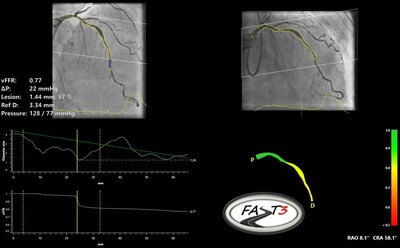

MAASTRICHT, Paesi Bassi, 18 giugno 2024 /PRNewswire/ -- Pie Medical Imaging, leader globale nell'imaging cardiaco, annuncia di aver completato l'arruolamento dei pazienti nel FASTIII, uno studio clinico randomizzato multicentrico, che studia l'uso della riserva di flusso frazionale dei vasi basata sull'angiografia (CAAS vFFR) in pazienti sottoposti a procedure di rivascolarizzazione coronarica. La vFFR può valutare se un restringimento dell'arteria coronaria è funzionalmente significativo e può richiedere una rivascolarizzazione.

FASTIII è il più grande studio di non inferiorità in corso (che vede arruolati 2228 pazienti), nel quale una strategia guidata da vFFR derivata angiograficamente viene confrontata con una strategia guidata da FFR per guidare la rivascolarizzazione coronarica. Il risultato complessivo primario valutato è un composito di tutte le cause di morte, di qualunque infarto miocardico o qualunque rivascolarizzazione ad un anno dalla randomizzazione.